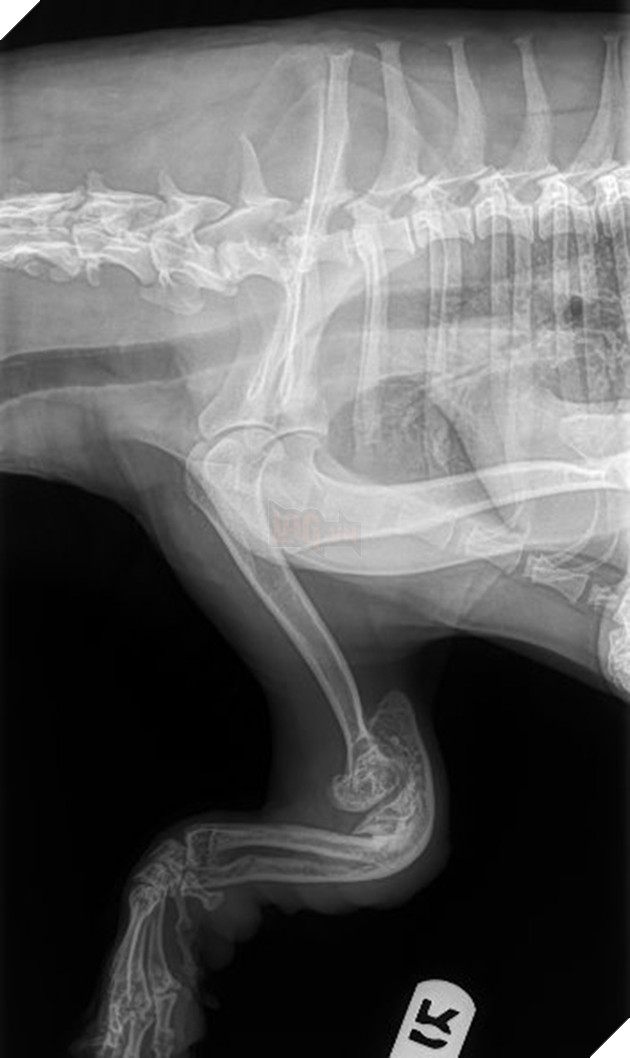

Thật đau lòng, Milhet nghĩ rằng chắc rằng cô chó này bị thương trong lúc chạy đến đây, vết thương nghiêm trọng hơn những gì mà cô đã từng nhìn thấy trước đây khi mà những chiếc móng mọc ngược đâm thẳng vào trong những đệm thịt của cô Husky này.

Theo chia sẽ của Natalie thì Lucky bị thương nghiêm trọng ở tứ chi và đó là kết quả của rất nhiều tai nạn kết hợp lại và rất khó để chữa lành hoàn toàn. Nếu không may mắn hơn thì tình trạng này lại có thể là bẩm sinh từ nhỏ và khi lớn lên đã trở nên nghiêm trọng hơn rất nhiều

Lucky đã có 1 khoản thời gian vô cùng khó khăn và đau đớn cho nên Lucia mong muốn Lucky có thể được phẩu thuật để tái cấu trúc lại tứ chi của cô chó nawy2. Tuy nhiên, các bác sĩ thú y chia sẻ rằng điều này sẽ vô cùng đau đớn và tỉ lệ thành công cũng khôn quá cao.

Nhóm tình nguyên viên này cũng đã đưa Lucky đến những bác sĩ thú y ngoại khoa tốt nhất trong khu vực nhưng việc tiến hành phẫu thuật cho Lucky vẫn không được khuyến khích vì cần phải thực hiện phẫu thuật rất nhiều lần và điều này quá đau đớn và vượt sức chịu đựng của 1 con chó Husky

Sau nhiều ý kiến, họ quyết định sử dụng chân giả được thiết kế đặc biệt cho đôi chân của cô. Thông qua đôi chân này, cô sẽ có được tự do lần thứ hai.